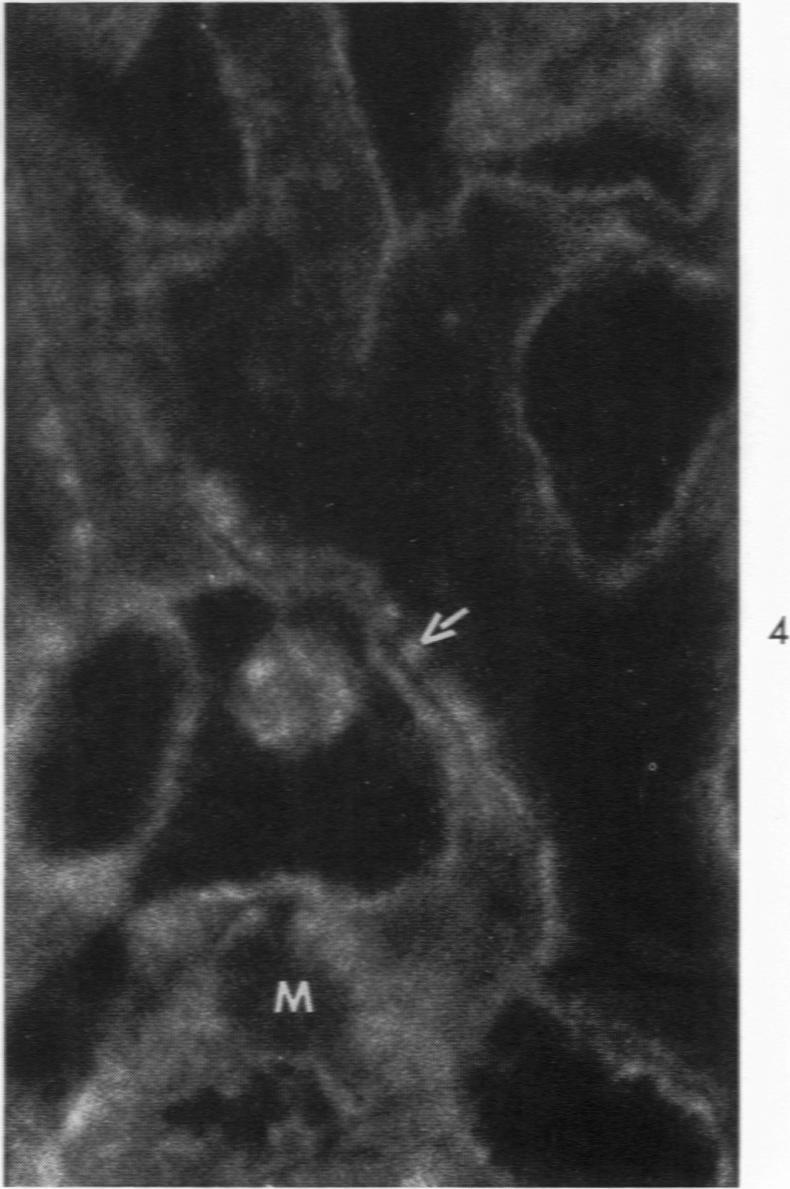

Experimental autoimmune nephrosis in rats. Morphogenesis of the glomerular lesion: immunohistochemical and electron microscopic studies.

Am J Pathol. 1969 Jan;54(1):47-71.

Experimental autoimmune nephrosis in rats. Morphogenesis of the glomerular lesion: immunohistochemical and electron microscopic studies.大鼠实验性自身免疫性肾病。肾小球病变的形态发生:免疫组织化学和电子显微镜研究。